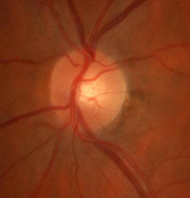

Il nervo ottico è costituito dall’insieme delle fibre nervose (circa un milione) che connettono la retina al cervello. La sua funzione è quella di trasmettere gli impulsi generati a livello retinico fino al cervello. Nel glaucoma si ha una perdita progressiva di queste fibre, con un conseguente quadro di atrofia del nervo.

A sinistra: nervo ottico sano. A destra: nervo ottico con atrofia glaucomatosa